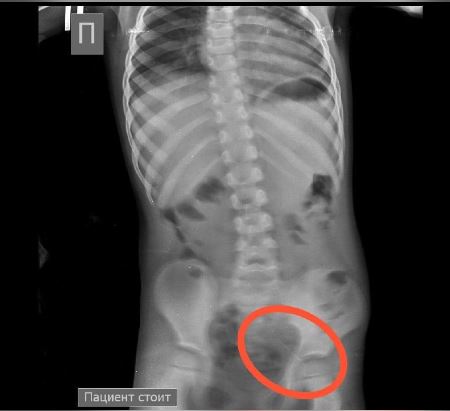

Ребенок продолжал находиться под наблюдением. На контрольной R–грамме брюшной полости обнаружена четвертая игла в проекции таза. Проведена колоноскопия и из сигмовидной кишки удалена последняя игла, которая концом была фиксирована в слизистую кишечника.